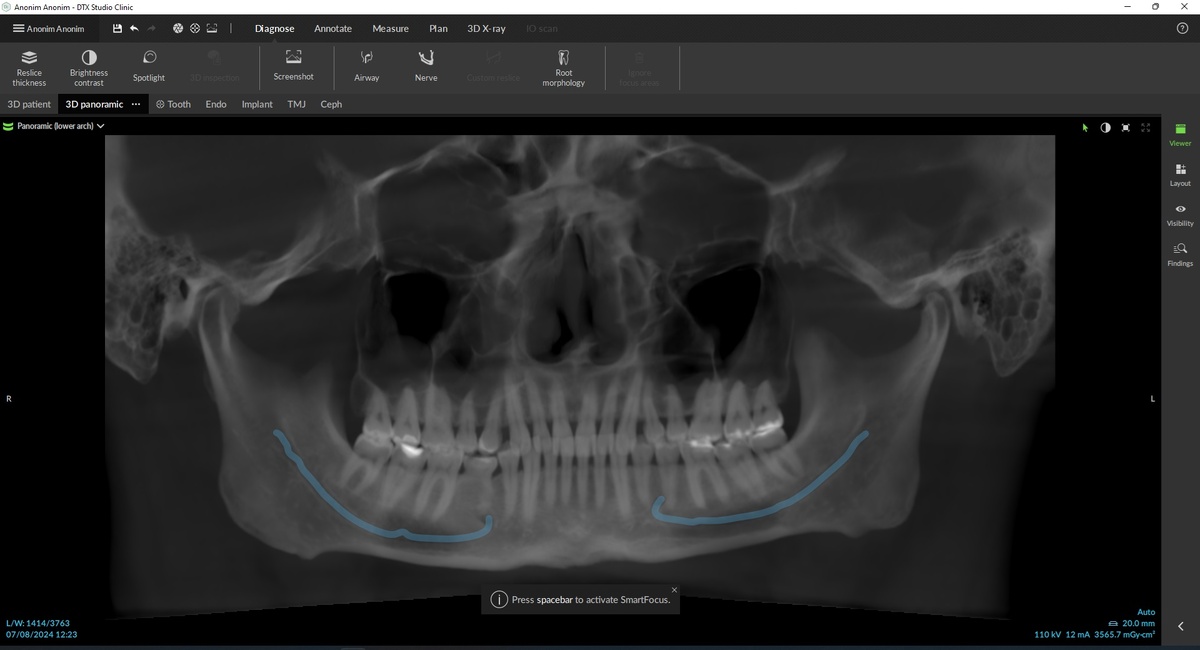

Обзорный снимок, на котором виден молочный зуб 8.5: